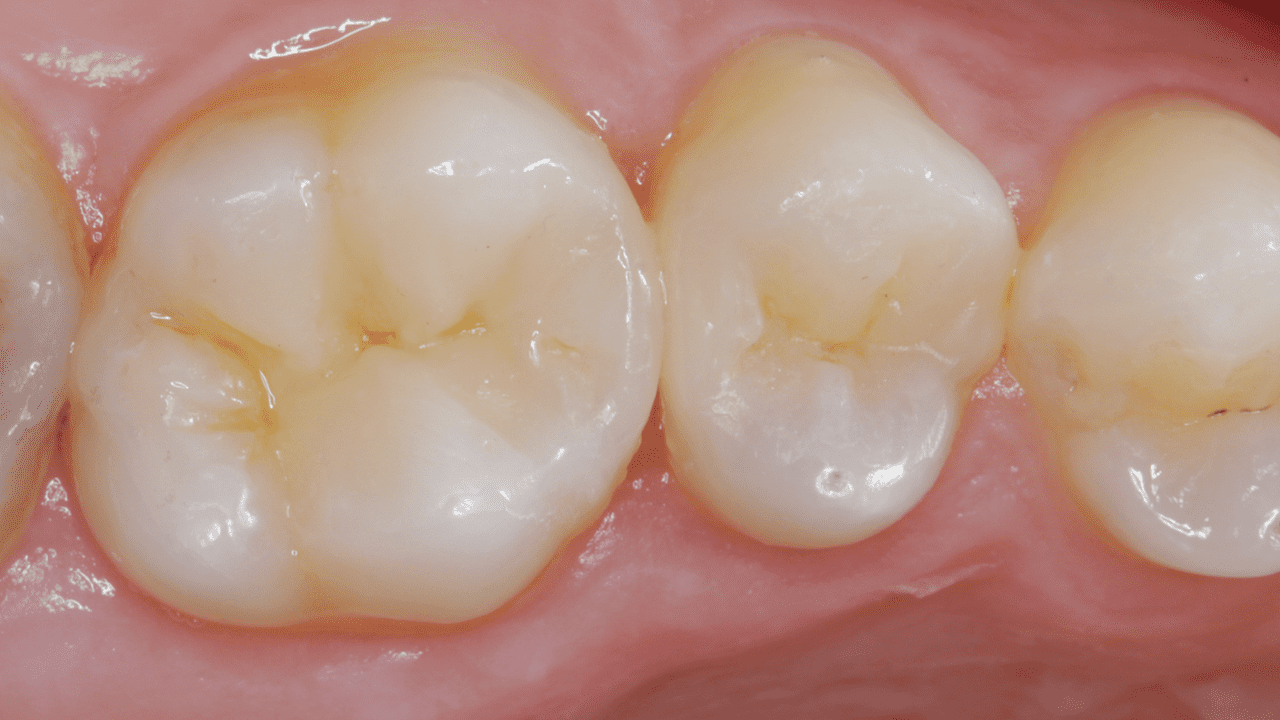

Results: Two-week recall. Final restoration and excellent gloss retention with Ceram.x Spectra ST universal composite A2 and BW giving the tooth back its lost anatomy and natural esthetic appearance.